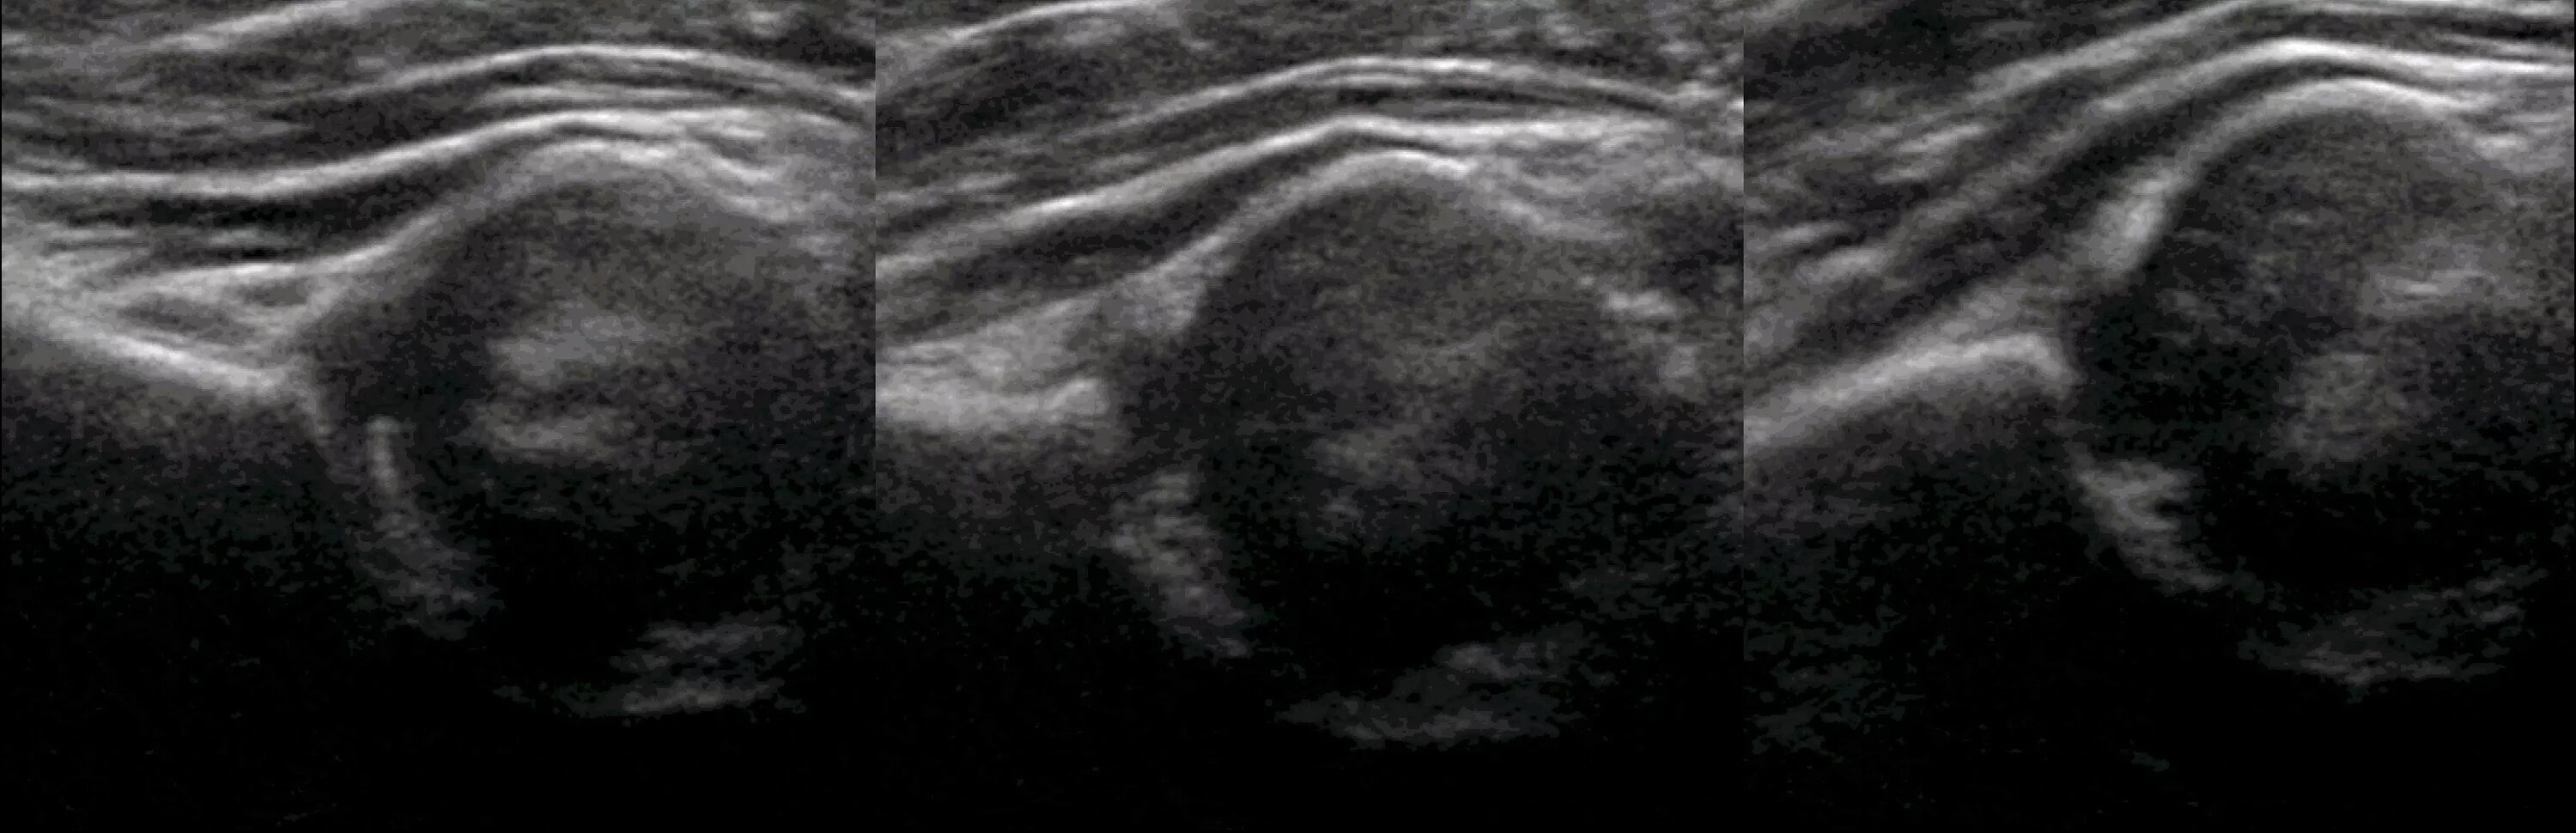

Делают ли узи тазобедренного сустава